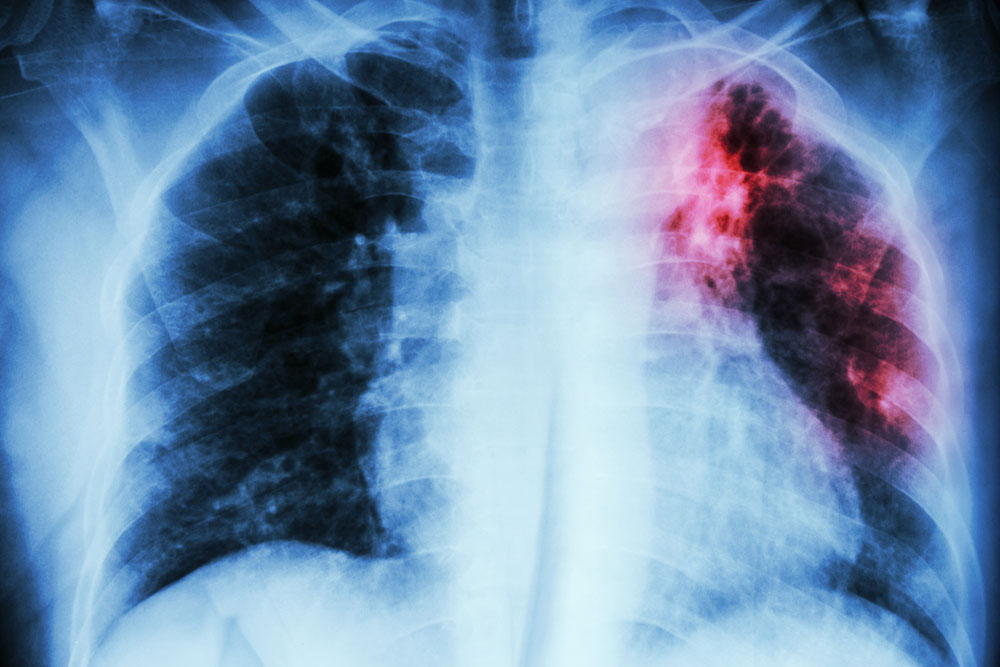

• Chest X-ray

This non-invasive technique provides a clear and detailed picture of your heart and lungs which the doctor can examine to detect any problem.